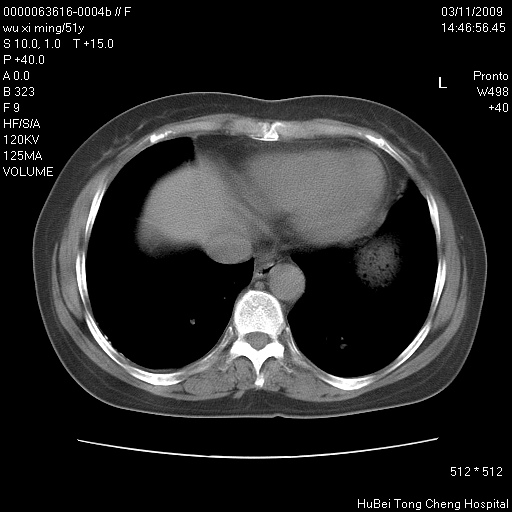

患者 女,51岁。因“胆囊炎,胆囊结石”,行常规术前胸部x线检查发现:右上肺结节病灶,建议行进一步检查。患者无咳嗽、咳痰及咯血等呼吸道症状,近期出现背部疼痛不适。

胸部ct轴位平扫(层厚10mm,螺距1.5,重建间隔10mm;部分层面:层厚3mm,螺距1.0,重建间隔3mm),图像如下:

右肺周围型肺癌伴肺内转移信胸椎转移

1、周围型肺癌。(毛刺正、血管束集征,分叶。)

集束征,胸膜牽拉征,毛刺,淺分葉高度提示ca.

右肺周围型肺癌伴肺内转移及胸椎转移。已无手术机会。